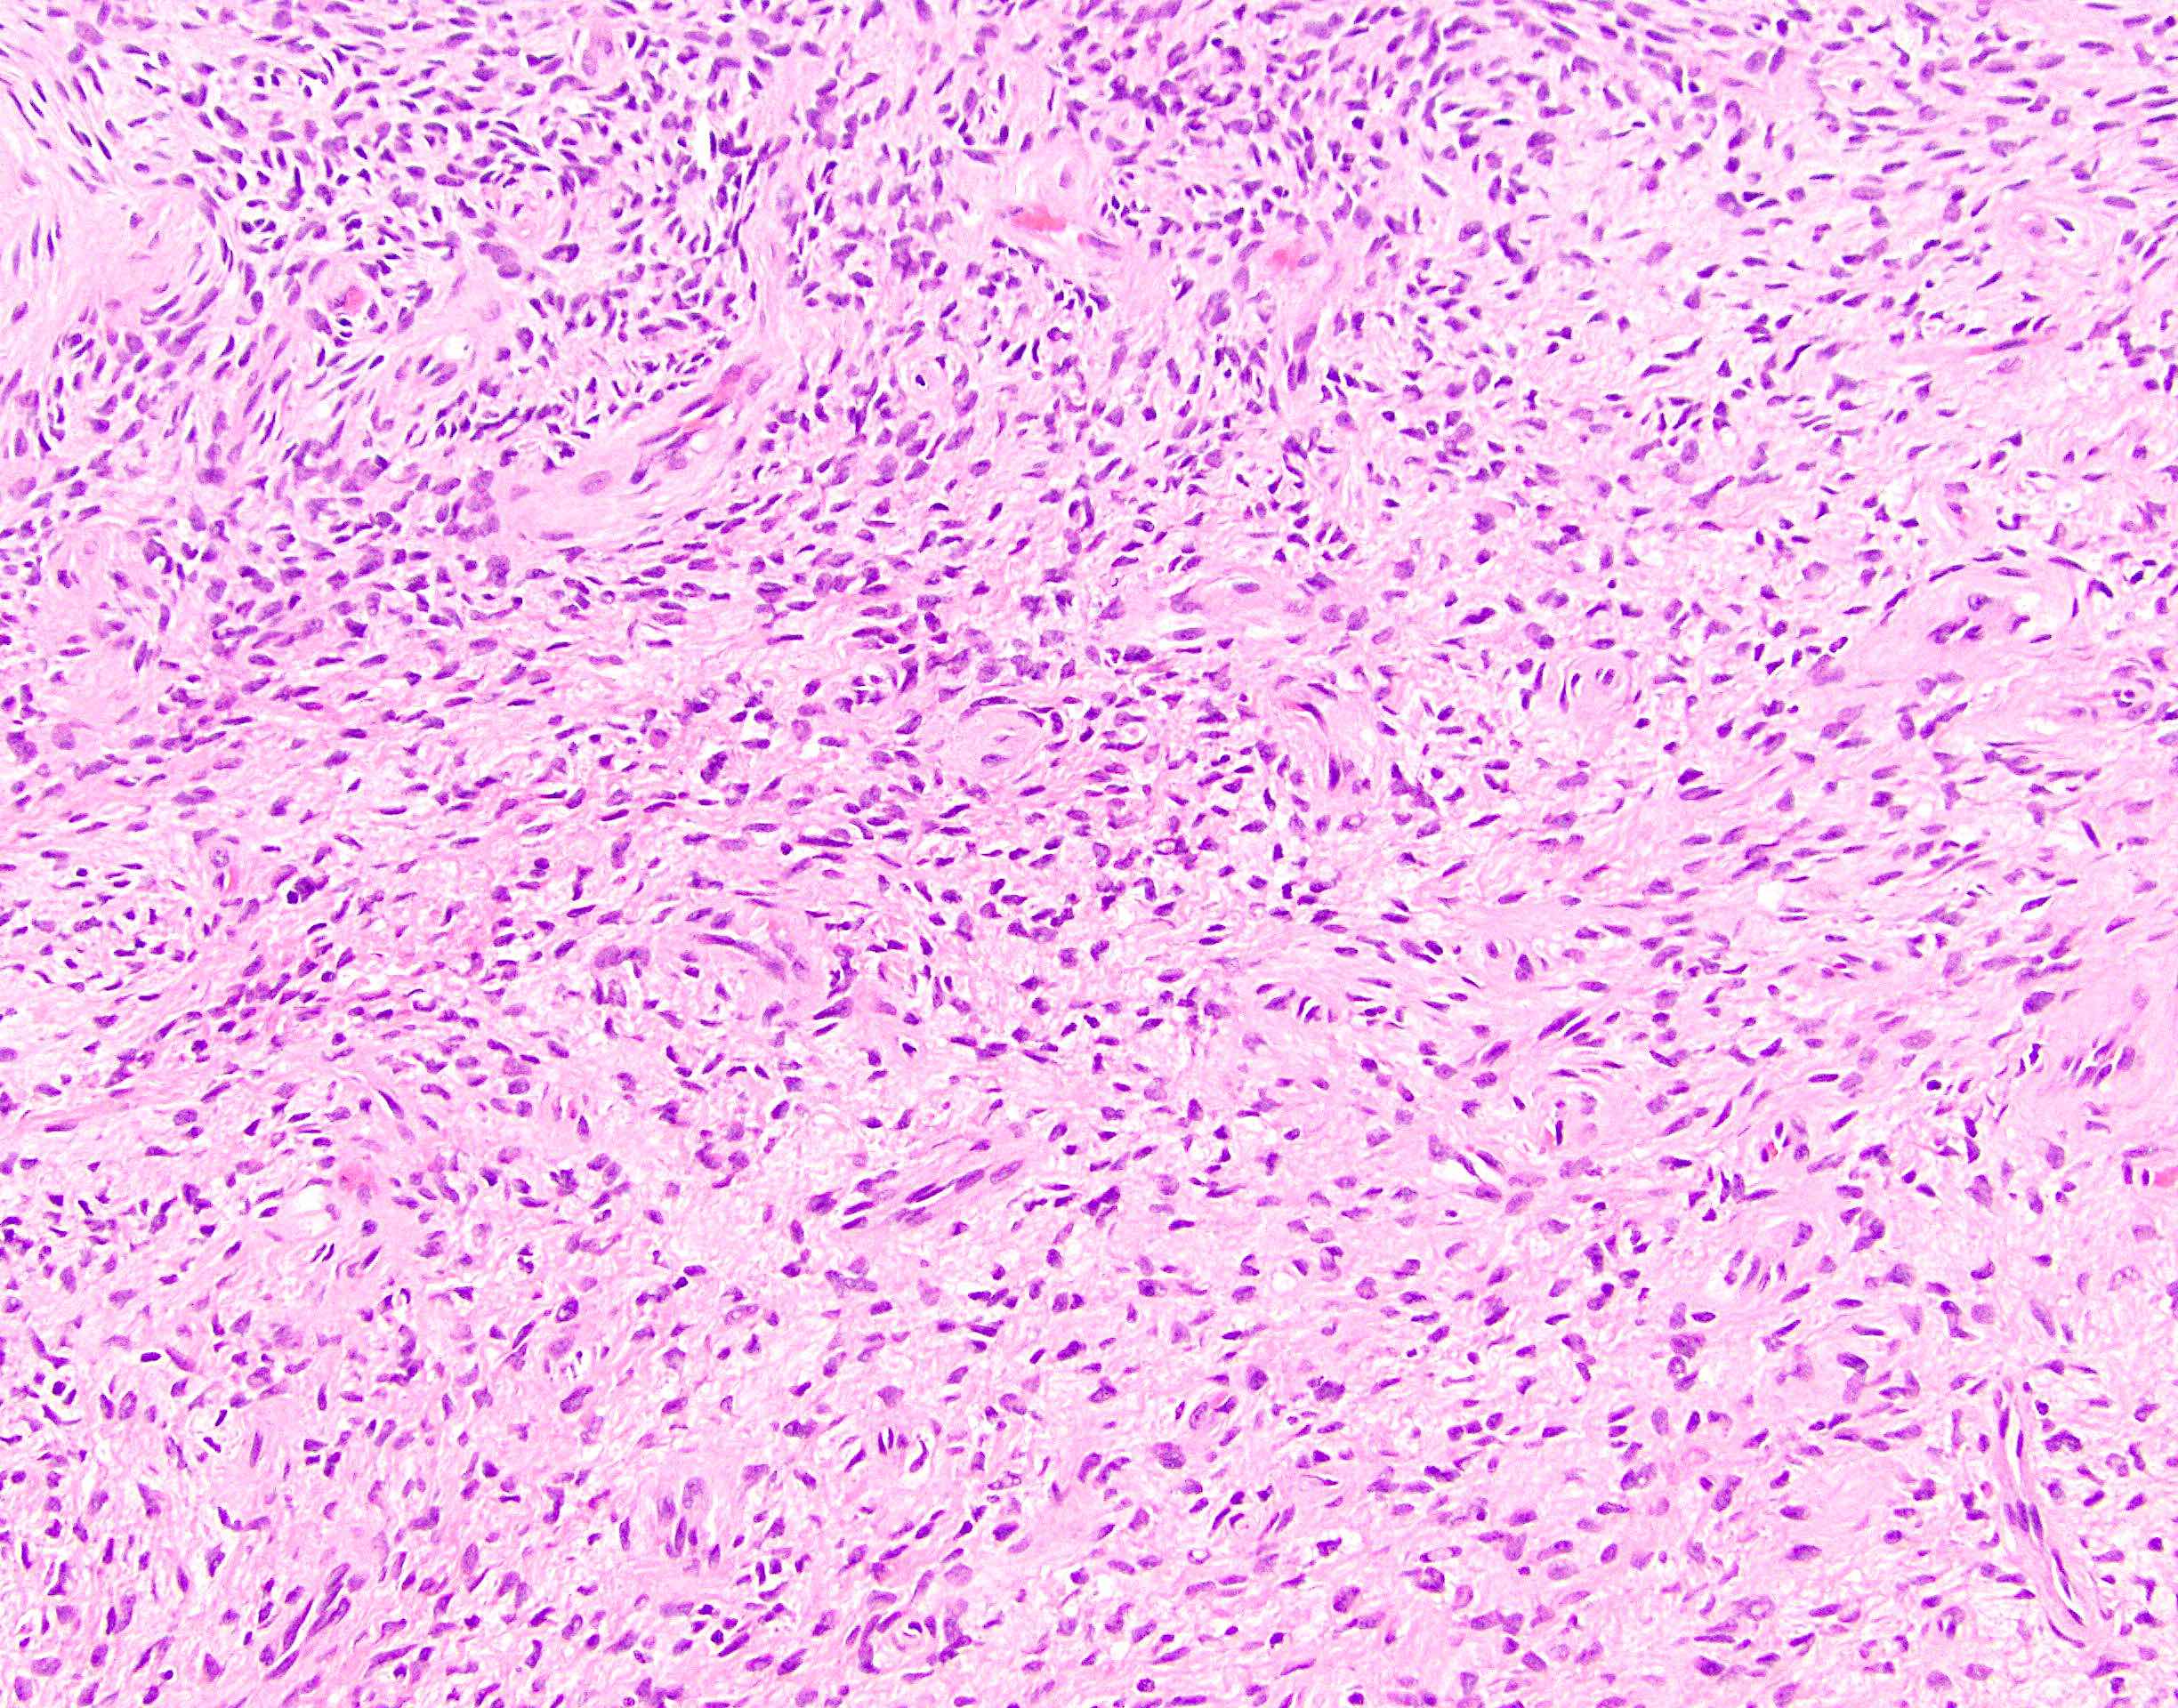

Microscopic (histologic) description

- Low to moderately cellular, bland fusiform or spindled cells with focal to diffuse whirling in heavily collagenized stroma with abrupt transition to myxoid areas

- 45% have epithelioid areas

- 40% contain poorly formed but large collagen rosettes

- Often infiltrates adjacent skeletal muscle

- Occasionally has areas of increased cellularity, atypia, necrosis or mitotic activity characteristic of intermediate to high grade sarcoma

- Recurrences may show increased cellularity and mitotic activity

Microscopic (histologic) images